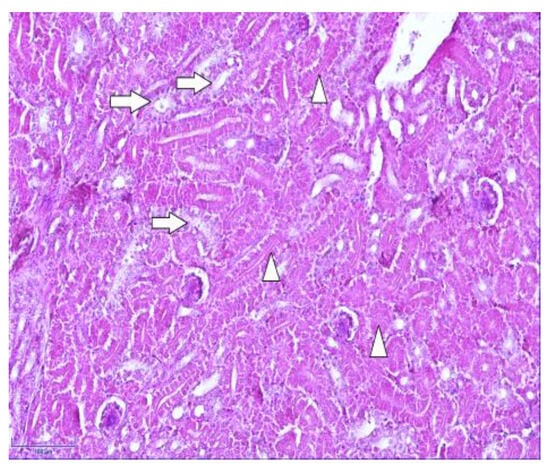

To facilitate an understanding of the normal chicken kidneys, routine histology staining using hematoxylin and eosin was carried out (Figure 2). In Figure 2, the identified proximal and distal renal tubules can be observed.

Figure 2. Normal kidney morphology of a 7-day-old chicken: proximal (arrowheads) and distal tubules (arrows) in the cortex of the kidney. Hematoxylin and eosin. Magnification 400×, scale bar 100 µm.